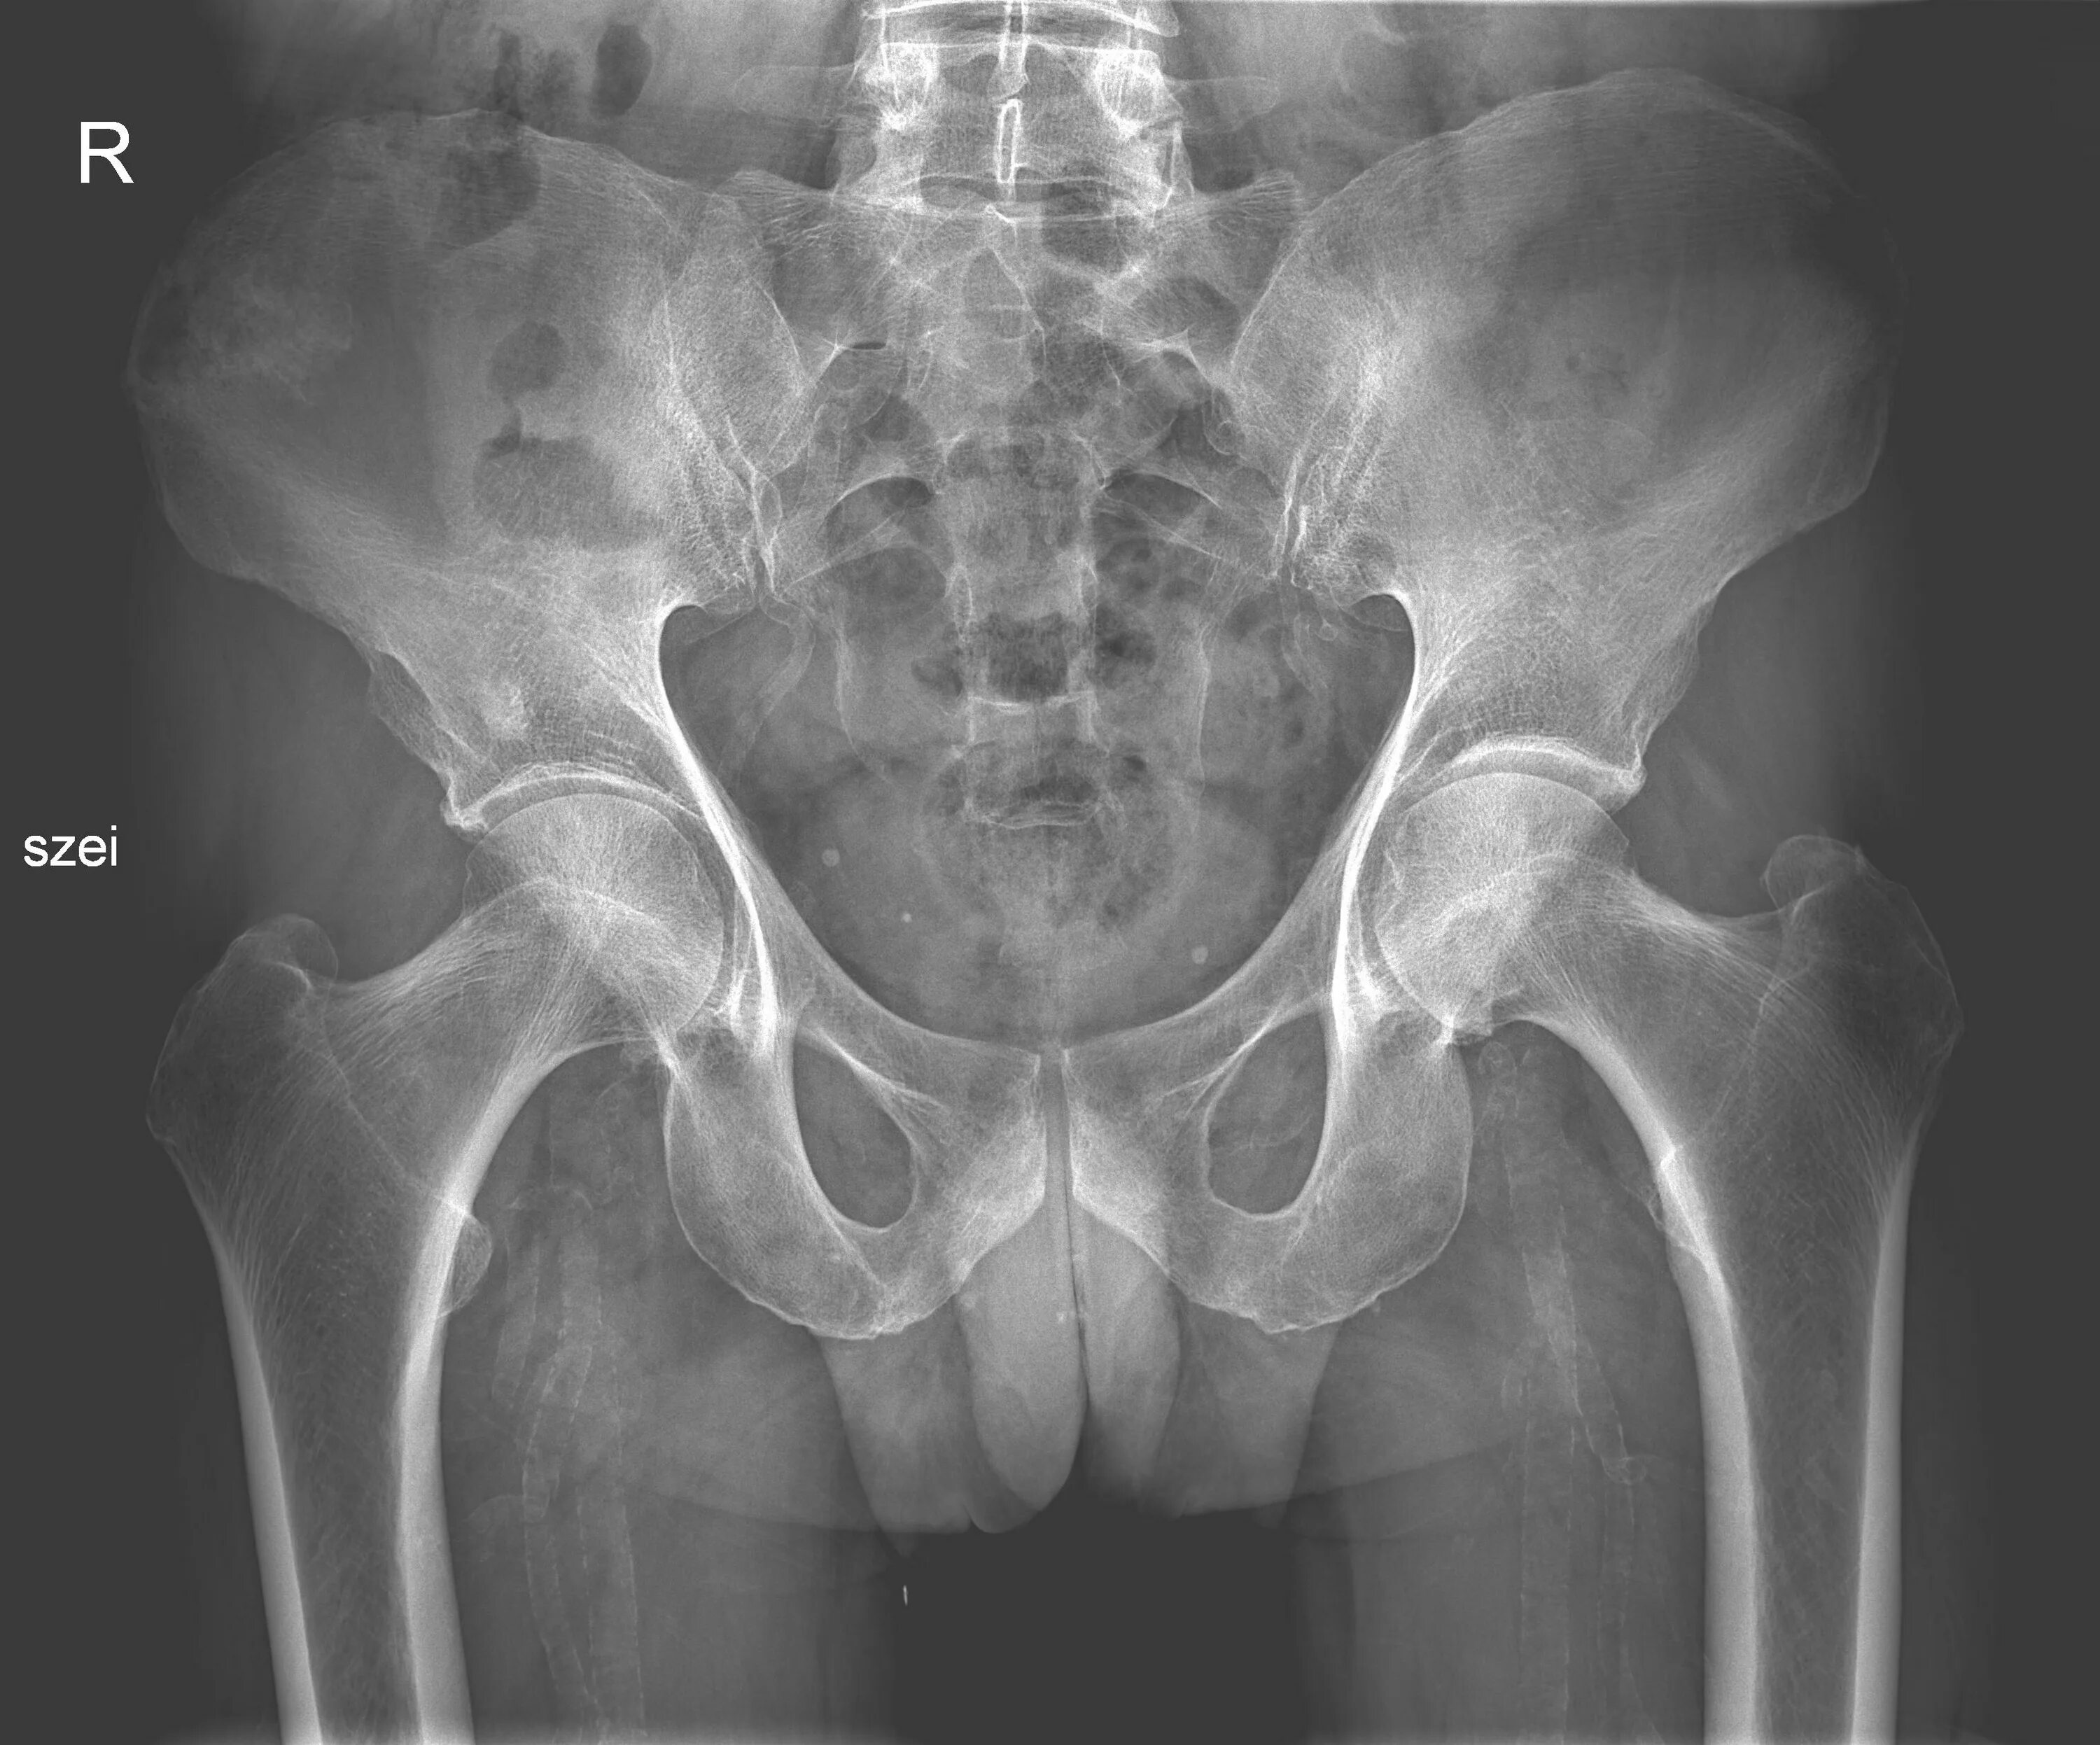

Снимок копчика